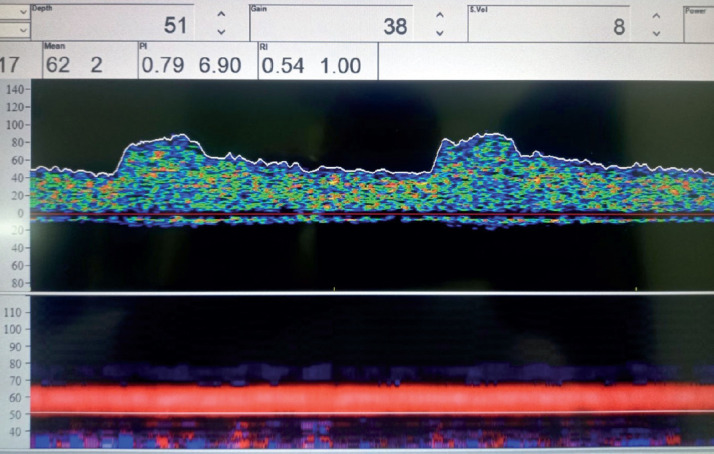

Background: Carotid atherosclerosis is often mentioned as one of the main causes of stroke. Currently, embolization is considered the most common mechanism that causes ischemic strokes due to atherosclerotic lesions in the carotid artery. Transcranial Doppler (TCD) ultrasound provides relatively inexpensive, noninvasive, real-time measurement of blood flow characteristics and cerebrovascular hemodynamics within brain arteries. The pulsatile index measured by transcranial Doppler is a parameter that indicates the degree of elasticity of the blood vessels of the brain.

Objective: The aim of this study is to determine the relationship between the value of the pulsatile index of the middle cerebral artery and the basilar artery in patients with carotid stenosis using transcranial Doppler and the value of the pulsatile index in relation to the degree of carotid stenosis.

Methods: The study involved a total of 140 patients examined at the Color Doppler and Transcranial Doppler Department of the Neurology Department of the General Hospital "Prim Dr. Abdulah Nakas" Sarajevo The patients were divided into two groups. The research was conducted in the General Hospital "Prim. dr. Abdulah Nakas" in Sarajevo at the Department for Color Doppler and Transcranial Doppler of the Department of Neurology and included patients examined in the period from February 2022 to December 2022. All patients underwent extracranial Doppler of the carotid arteries and transcranial Doppler of the middle cerebral artery and basilar artery.

Results: The mean values of PI in ACM in the total sample were statistically significantly lower in patients with stenosis up to 50% compared to the average in patients with stenosis over 50%. Average values of PI in AB in the total sample were statistically significantly lower in patients with stenosis up to 50% compared to the mean values in patients with stenosis over 50%.

Conclusion: Transcranial Doppler findings showed an increased pulsatile index in patients who had carotid stenosis greater than 50% compared to patients with mild carotid stenosis. The study showed that in clinical work it would be necessary to introduce the pulsatile index as an indispensable neurosonological parameter that would be included in the findings of the transcranial Doppler and thus objectify the potential risk of a cerebrovascular ischemic event.